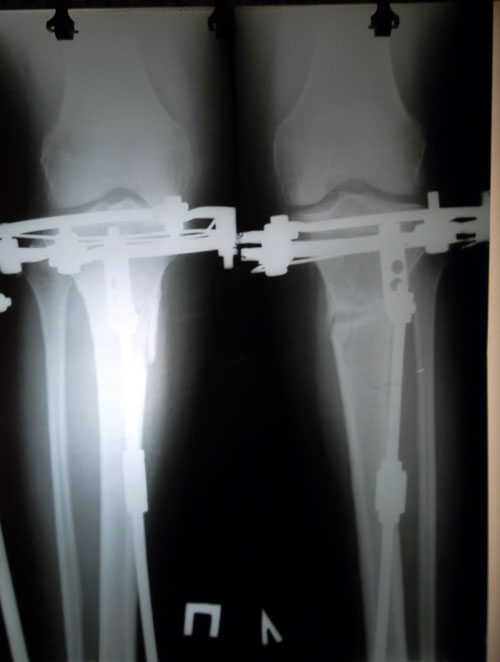

Дата операции 01.07.2014г.

Дата снятия аппаратов 17.10.2014г.

Срок лечения 97 дней.